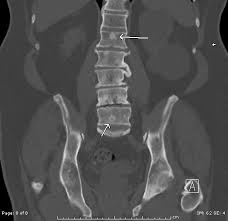

Bone Metastases Radiology Key

Bone Metastases Radiology Key from radiologykey.com